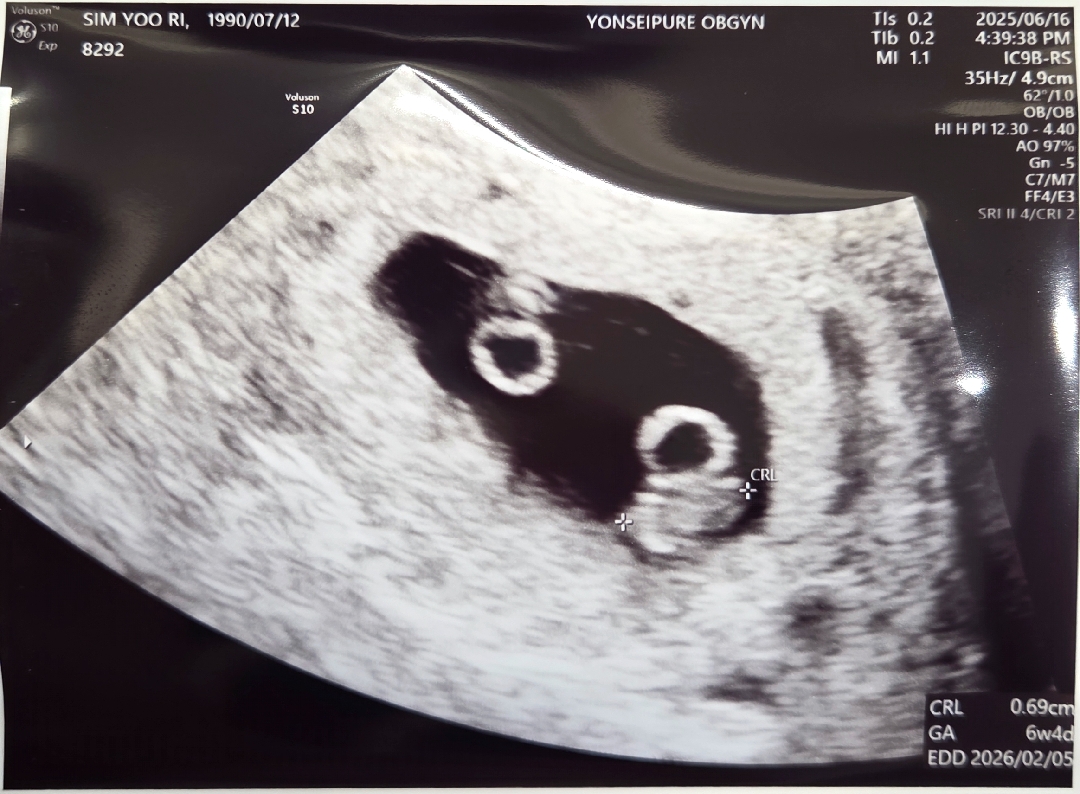

일란성 쌍둥이 당첨 ! 걱정반 설렘반이네요 >__<

심장소리 첨 들었어요. 눈물나는 거 참았네요 ㅠㅠ 어떻게 저에게 이렇게 아기천사가 둘이나 와줬는지 기특하기도 하고 감사하기도 하고.. 다태아 변경 신청 해야겠어용 단일 융모막 양막 같다고 그러셔서 걱정 많이 되구, 아직 지나면 양막이 보일수도 있대서 기다려보자 하시구.. 이제 대학병원으로 전원 확정이네유

와 난황도 또렷하고 넘 축하드려요! 혹시 몇주차신가요? 저번주에 난황만 보고와서 애기 보이는거보니까 신기하네요 ㅎㅎ

아기집은 7주1일인데 아기는 6주4일이래요~!